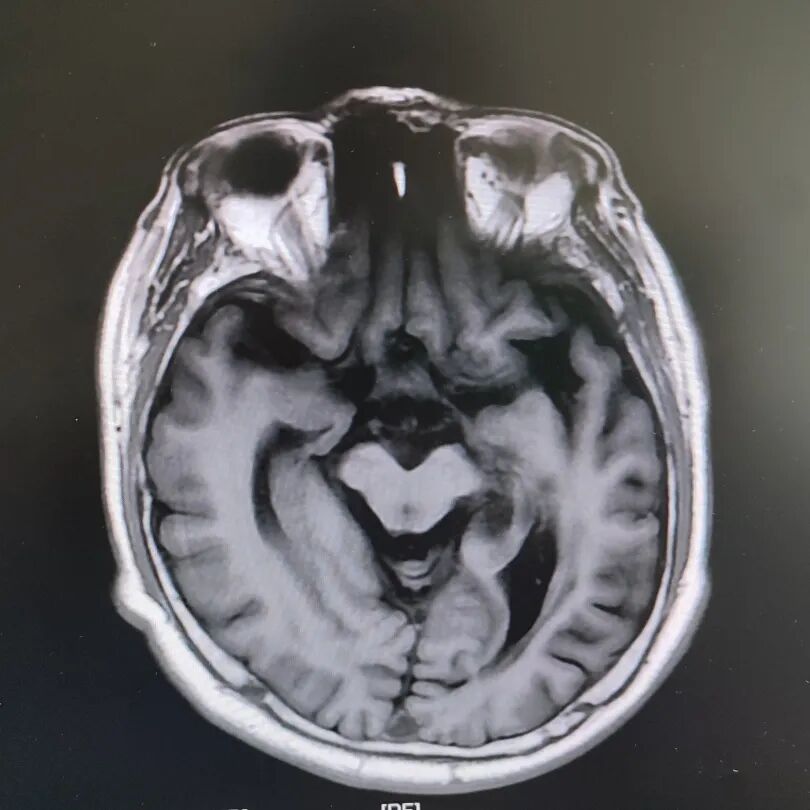

患者头部磁共振影像

凭着多年诊治疑难杂症的丰富经验,赵主任敏锐地意识到这“痴呆”可能是假象,背后另有隐情。他果断建议进一步做特殊感染筛查。果然,检查证实这位患者同样是感染了苍白密螺旋体!经过精准的抗感染治疗,奇迹发生了:患者的反应变快了,眼神灵活了,走路也恢复了正常步态。最终的诊断是“麻痹性痴呆”——一种由神经梅毒引起的、可治疗逆转的“痴呆”类型!